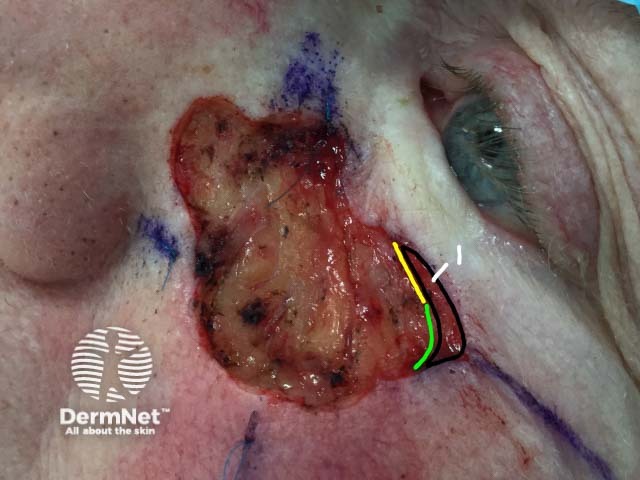

In the fifth Mohs stage the area to be excised is marked on the patient

The marked area is excised

The area is free of tumour cells